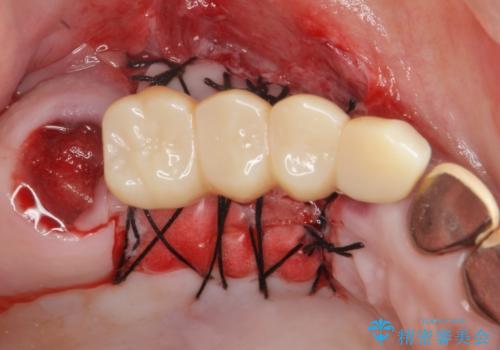

- 他院で1本インプラントを入れたまま治療に通うことができなくなり、途中からの治療を希望され来院されました。

既に埋入されているインプラントは位置が悪いのでそのまま骨内に留置することとし、新たに咬合機能を回復すべく3本のインプラントを埋入すると同時に吸収した骨幅を増やし、安定してインプラントで噛める環境整備を目指します。

- 120万円(インプラント×3 チタンカスタムアバットメント×3 メタルボンドクラウン×3 骨造成 歯肉移植)費用は治療当時の料金となります

インプラントが長持ちするために、インプラント周囲の十分な骨量・角化歯肉の存在・安定した咬合を一つづつ整備する治療を行いました。